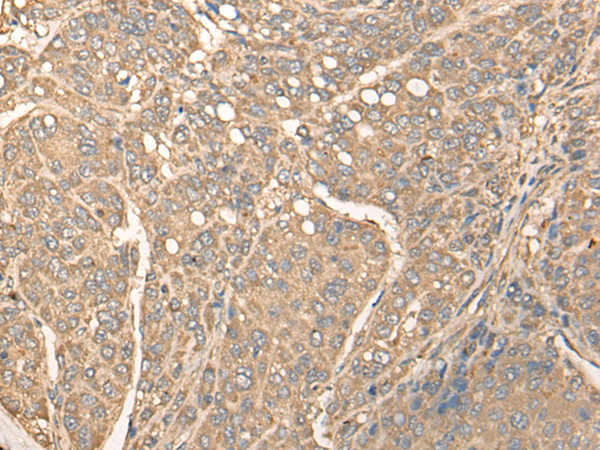

分类: 科研抗体货号: P02388别名: LGS应用: IHC反应种属: Human, Mouse